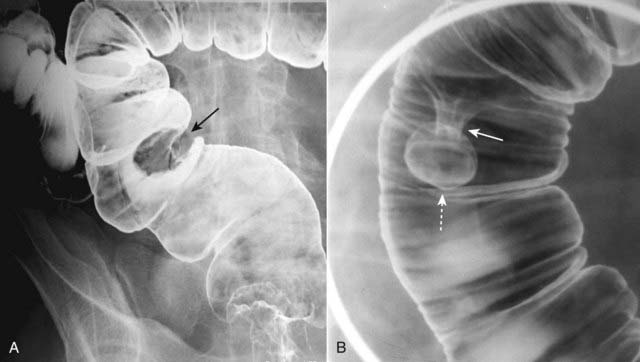

Figure 18-16 Sessile and pedunculated polyps of the colon.

Polyps can be recognized as persistent filling defects in the colon; barium is displaced by the polyp. A, There is a sessile filling defect in the pool of barium along the left lateral wall of the sigmoid colon (solid black arrow). The size of the lesion should raise concern for malignancy. B, In another patient with a filling defect in the sigmoid colon etched by barium (dotted white arrow), the polyp is seen to be attached to the wall of the colon by a stalk (solid white arrow). Polyps on a stalk are called pedunculated polyps.